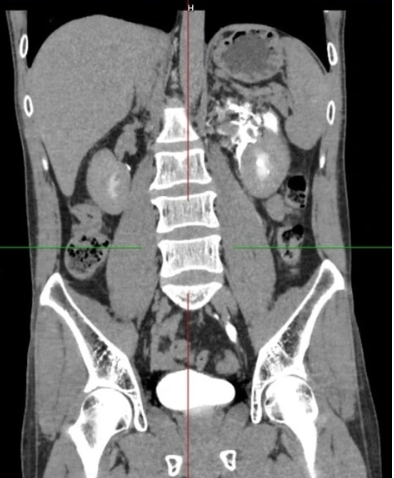

Kết quả siêu âm và CT-Scanner khẩn cấp cho thấy một viên sỏi kích thước khoảng 4 mm kẹt ở 1/3 dưới niệu quản trái, gây tắc nghẽn hoàn toàn ḍng nước tiểu từ thận xuống bàng quang.

Theo bác sĩ Mai Văn Lực, khoa Phẫu thuật Thận Tiết niệu - Nam học, Bệnh viện E, dù thông thường sỏi nhỏ có thể được điều trị nội khoa để tống sỏi ra ngoài, nhưng trong trường hợp này, tắc nghẽn đột ngột khiến áp lực trong đài - bể thận tăng cao, dẫn đến vỡ bể thận - niệu quản. Nước tiểu thoát ra khoang sau phúc mạc, bao quanh thận trái với số lượng lớn, đe dọa nhiễm trùng huyết và suy thận cấp.

Vỡ bể thận niệu quản trái, thoát nước tiểu quanh thận trái. Ảnh: BVCC.